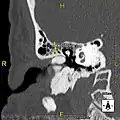

Normal ear canal

The normal ear canal is approximately 7 mm in diameter and has a volume of approximately 0.8 ml (approximately one-sixth of a teaspoon).[5] As the condition progresses, the diameter narrows and can even close completely if untreated, although people generally seek help once the passage has constricted to 0.5–2 mm due to the noticeable hearing impairment. While not necessarily harmful in and of itself, constriction of the ear canal from these growths can trap debris, leading to painful and difficult to treat infections.